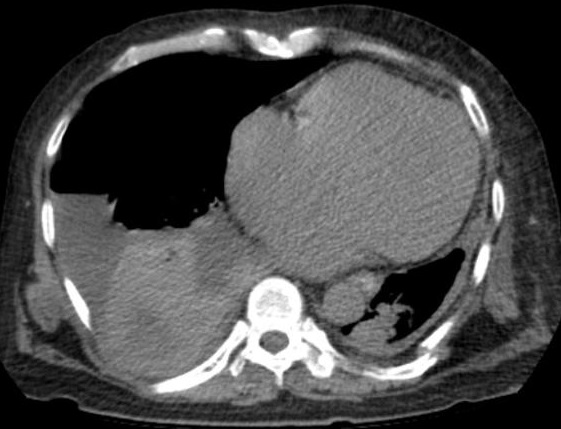

Aspect radiologique TDM d'une

hydro -pneumo thorax du poumon droit . Image en

niveau hyperdense à la base du poumon droit est en

vue trè nette sur ce coupe .La limite de la plevre

visceral du poumon droit est preque n'a pas en vue

peu en differencie avec espace hydro-pneumothorax

facille . Image radiologique TDM en coupe

axial fenetre osseuse |

Image radiologique TDM fenetre parenchymateuse

d'une hydro-pneumothorax du poumon gauche avec

aspect de image hydro-aerique incline à gauche

. La limite de la plevre visceral du poumon gauche

gauche très facille |